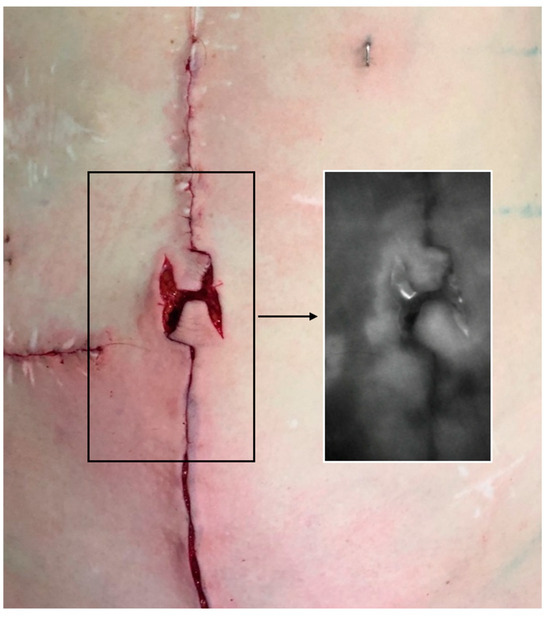

We encountered three wound healing complications. Two were minor wound healing disorders (Clavien–Dindo Grade I) involving the T-scar, and the omphaloplasty was unaffected in both cases. One patient experienced a more severe wound healing complication involving the vertical scar and the lower flap of the neo-umbilicus (Clavien–Dindo Grade IIIb). The patient suffered from severe pre-existing illnesses, including ascites from liver cirrhosis, Diabetes Type 2, and C2-abuse and was a heavy smoker. We opted for an early revision and decided to reconstruct the lower part of the umbilicus with a skin graft from the groin rather than waiting for secondary wound healing (Figure 6a,b). Healing after revision was prolonged. The patient presented a superficial necrosis lateral to the vertical scar in the lower abdomen, 2.5 cm below the neo-umbilicus. The neo-umbilicus itself healed without complications after skin grafting (Figure 6c,d). We did not encounter any case of umbilical flattening or detachment of the anchorage stitches from the fascia.

Figure 6. (a,b) Pre- early postoperative result. (a) 66-year-old patient with instable abdominal scarring and chronic fistula after multiple abdominal surgeries including recto-sigmoid resection, partial bladder resection, hernia repair, and multiple revisions after adhesive ileus of the small intestine. Pre-existing illnesses included diabetes Type 2, C2- and nicotine-abuse, and liver cirrhosis. (b) This patient experienced a Type IIIb wound healing complication involving the vertical scar and the lower flap of the neo-umbilicus. We opted for an early revision and decided to reconstruct the lower part of the umbilicus with a skin graft rather than waiting for secondary wound healing. Figure 6c,d show the postoperative result after 12 months, with the (c) full frontal and (d) 45° oblique view. The patient presented a superficial necrosis lateral to the vertical scar in the lower abdomen, 2.5 cm below the neo-umbilicus in the postoperative course. The neo-umbilicus itself healed without complications after skin grafting. The neo-umbilicus sustained sufficient depth and adequate shape. The patient rated the result as “good”, while the physicians rated the result as “average”. Retrospectively, in this case we should have opted for a simple skin grafting technique in the first place or decided against immediate umbilical reconstruction during abdominal wall reconstruction entirely.